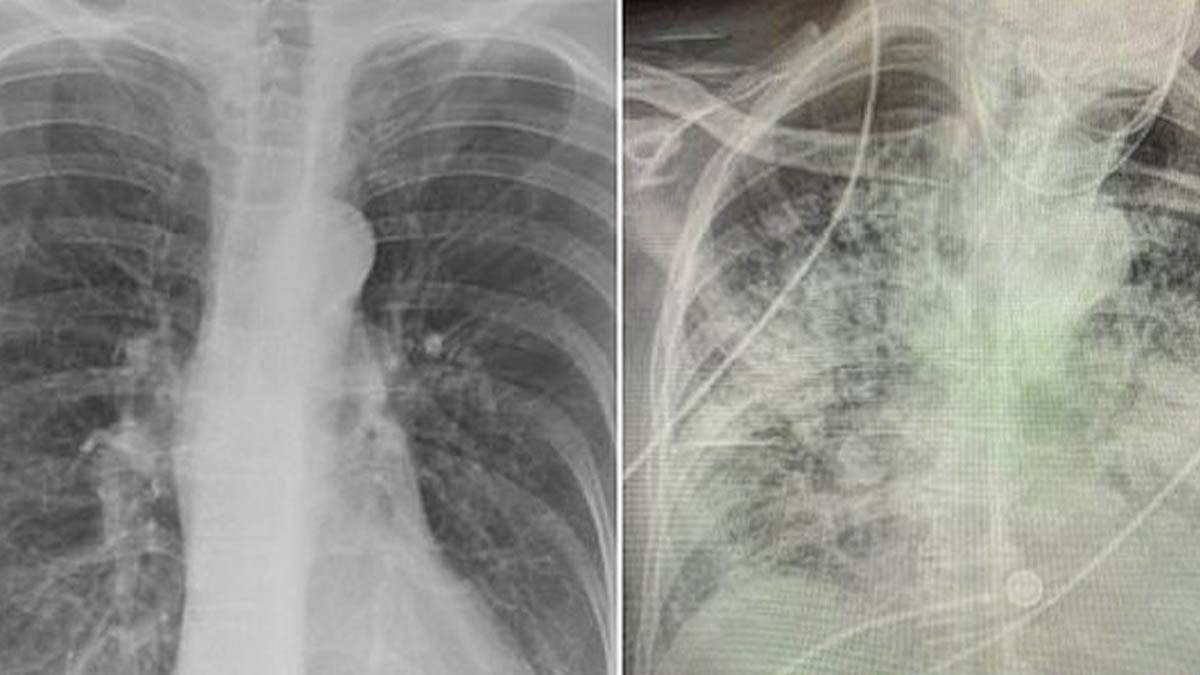

Akciğerler, sigaranın etkilerinin en belirgin görüldüğü organdır; sigara içmek akciğerlerin görünümünü değiştirir, kararmasına, elastikiyet kaybına ve iltihaplanmasına neden olur.

Uzun süreli sigara içenlerde bu hasarların bir kısmı geri döndürülemez olsa da, sigarayı bırakmak her zaman sağlığımızı iyileştirmek için en etkili adımlardan biridir. Sigara içmeyi bırakan kişiler, vücutlarının neredeyse anında iyileşmeye başladığını hissederken, akciğerlerin durumu gibi önemli gelişmeler zamanla daha belirgin hale gelir.